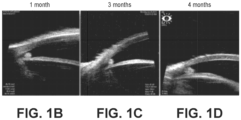

- FIGs. 1A are ultrasound images of a hydrogel depot in the anterior chamber of the eye, in the iridocorneal angle, in a beagle, at 1 month, 3 months and 4 months post-placement.

- Figs. 1A-1D depict a crosslinked matrix that is a hydrogel in an anterior chamber of the eye, in the iridocorneal angle.

- the depots in the anterior chamber were easily visualized using a slit lamp or blue light with yellow filter through 56 days. By day 84 the hydrogel portion of the depot had fully degraded and no fluorescence of the depot was evident. The travoprost microparticles remained and continued to deliver drug to the anterior chamber demonstrating pupil constriction as a pronounced pharmacodynamic affect.